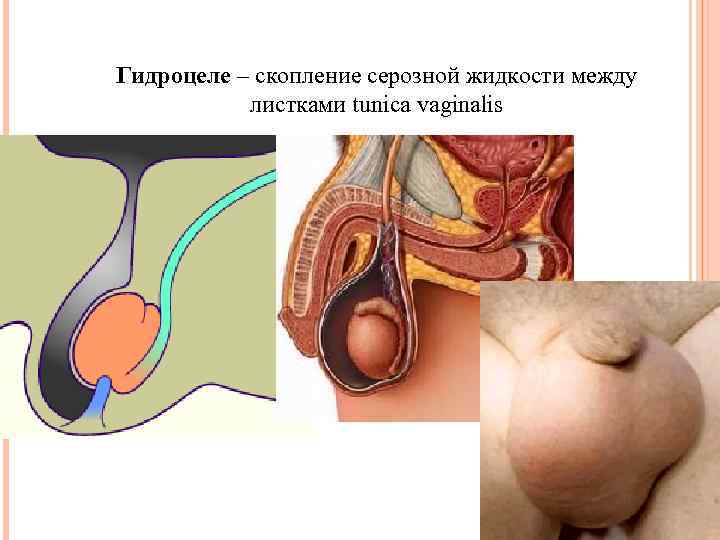

Гидроцеле – скопление серозной жидкости между листками tunica vaginalis

Гидроцеле – скопление серозной жидкости между листками tunica vaginalis